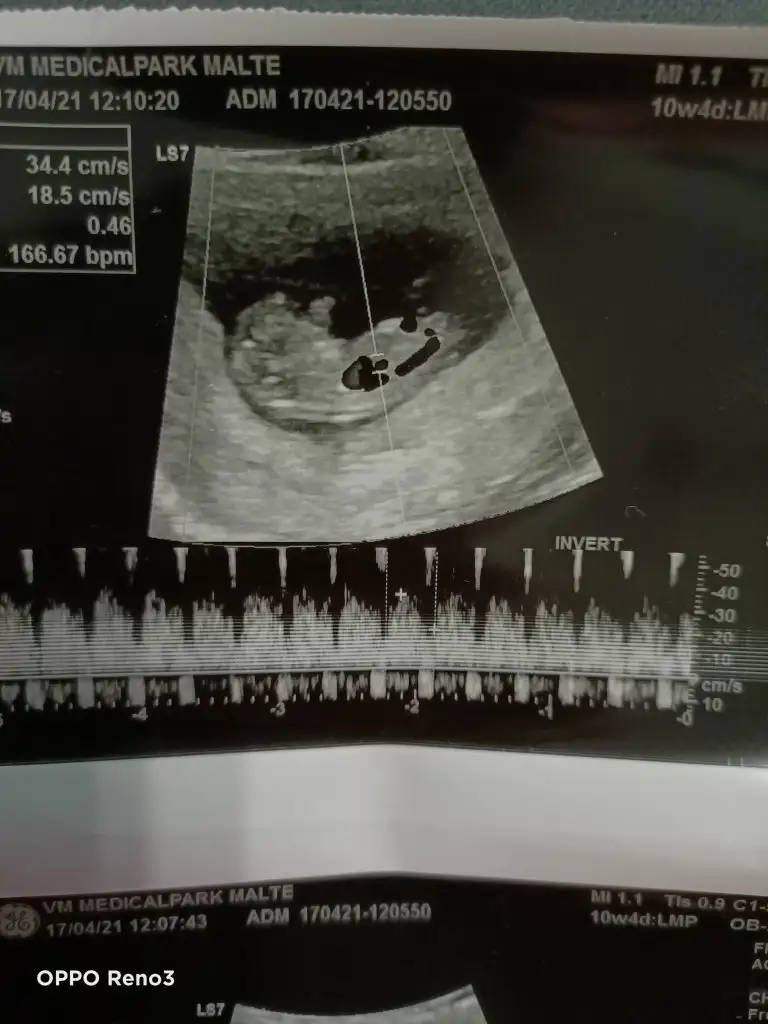

Tahminde bulunurmusun